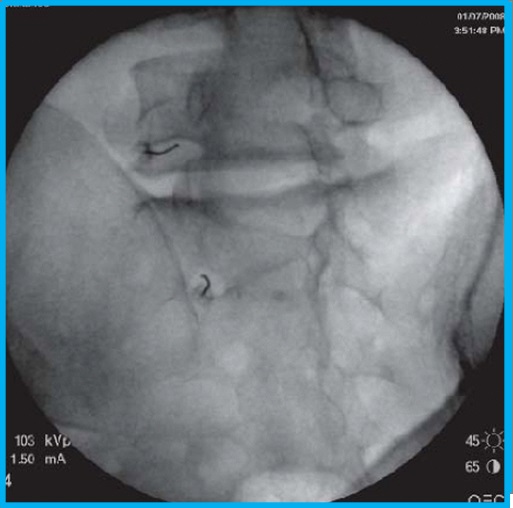

Η ουραία επισκληρίδιος έγχυση είναι η χορήγηση κορτιζόνης και τοπικού αναισθητικού μέσω του ιερού τρήματος που αποτελεί το κατώτερο τμήμα της σπονδυλικής στήλης. Μέσω του τρήματος μπορεί να γίνει μεμονωμένη έγχυση ουσιών ή να εισαχθεί επισκληρίδιος καθετήρας που θα κάνει συγχρόνως και λύση τυχόν συμφύσεων σε περιπτώσεις μετεγχειρητικού άλγους.